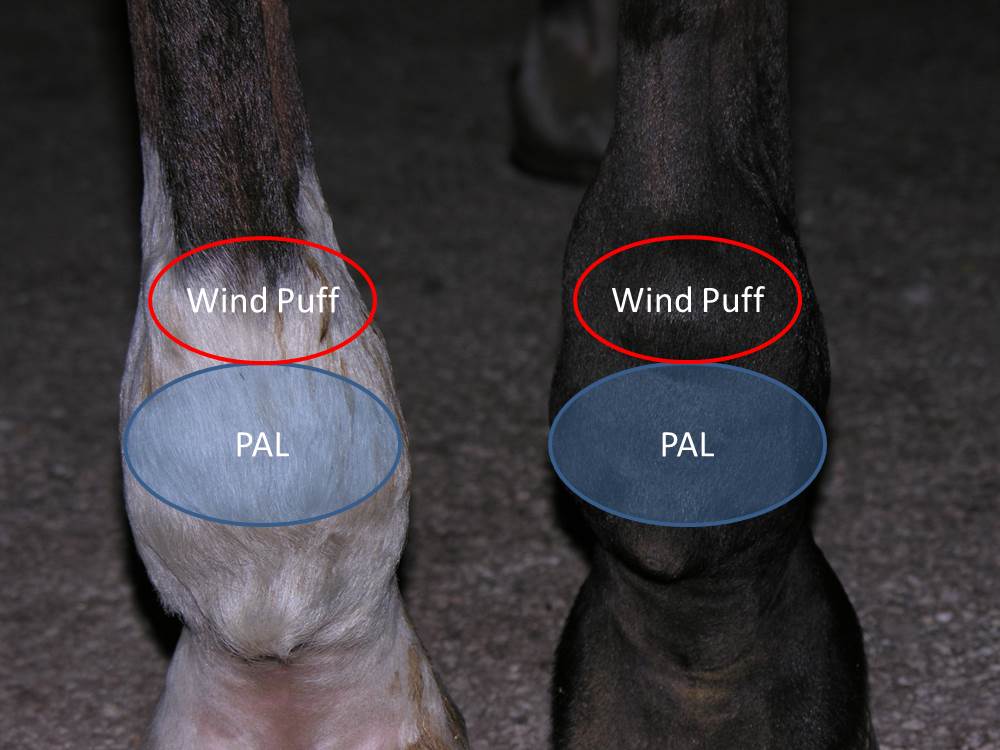

ar.inspiredpencil.comMichael Porter, Equine Veterinarian: Plantar Annular Ligament Desmitis

ar.inspiredpencil.comMichael Porter, Equine Veterinarian: Plantar Annular Ligament Desmitis

michaelporterdvm.blogspot.complantar horse ligament annular equine

mungfali.comTendonous Windgall Worries

mungfali.comTendonous Windgall Worries

www.vrogue.coMichael Porter, Equine Veterinarian: Plantar Annular Ligament Desmitis

www.vrogue.coMichael Porter, Equine Veterinarian: Plantar Annular Ligament Desmitis

michaelporterdvm.blogspot.co.ukligament horse annular equine plantar ultrasound pal veterinarian porter michael figure

michaelporterdvm.blogspot.co.ukligament horse annular equine plantar ultrasound pal veterinarian porter michael figure

ar.inspiredpencil.comMichael Porter, Equine Veterinarian: Plantar Annular Ligament Desmitis

ar.inspiredpencil.comMichael Porter, Equine Veterinarian: Plantar Annular Ligament Desmitis

michaelporterdvm.blogspot.comligament annular plantar horse equine pal porter veterinarian michael figure lameness

michaelporterdvm.blogspot.comligament annular plantar horse equine pal porter veterinarian michael figure lameness